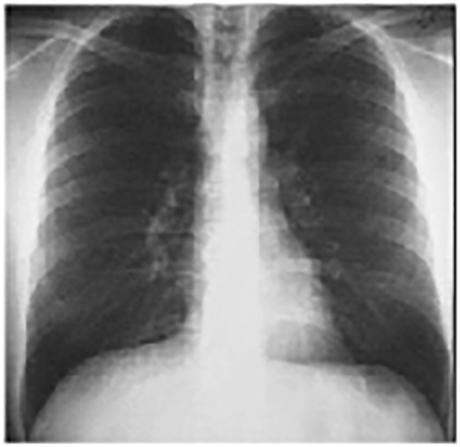

PA and Lateral

Click on the Xrays to enlarge them.

Choose the best interpretation of the chest X rays:

Entirely normal